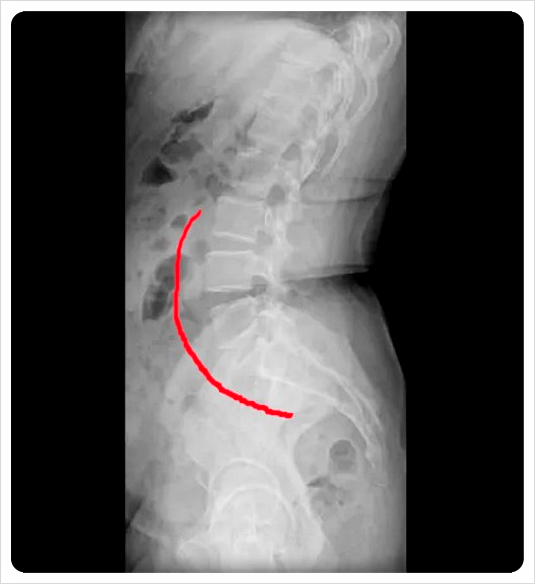

전방 경사는 골반 앞쪽이 아래로 내려가고 뒤쪽이 올라간 형태, 후방 경사는 그 반대로 뒤쪽이 내려간 상태를 말합니다.

허리 전만·후만 변화